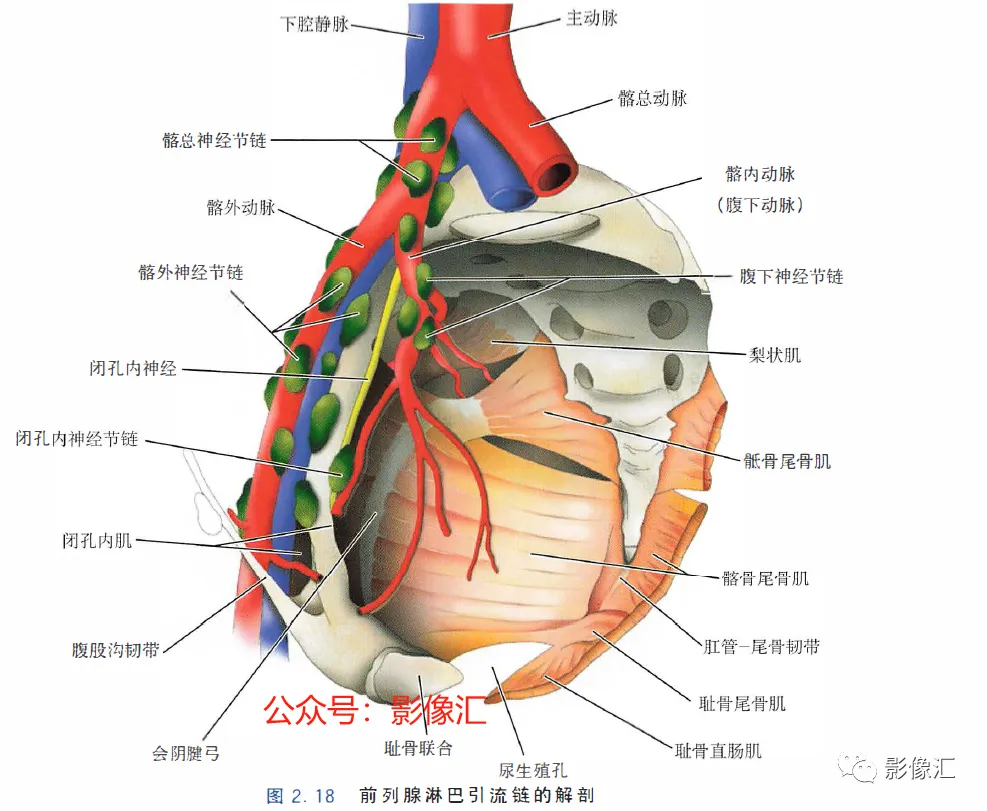

小的叶间毛细淋巴管相互吻合,形成直径逐渐增大的淋巴引流网络,直至穿过前列腺包膜并形成密集的前列腺周围淋巴引流网络。最终通过不同的途径回流到闭孔内动脉、髂外动脉、髂总动脉、腹下动脉和骶前淋巴结的淋巴链。1. 冠状面(图2.19)